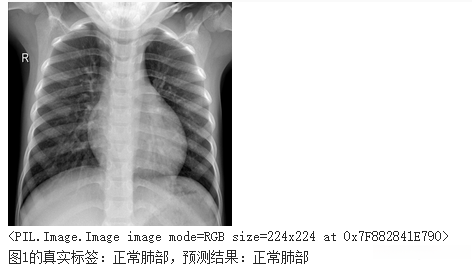

print("图%d的真实标签:%s,预测结果:%s" % (idx+1, truth_lab, infer_lab))

结果展示